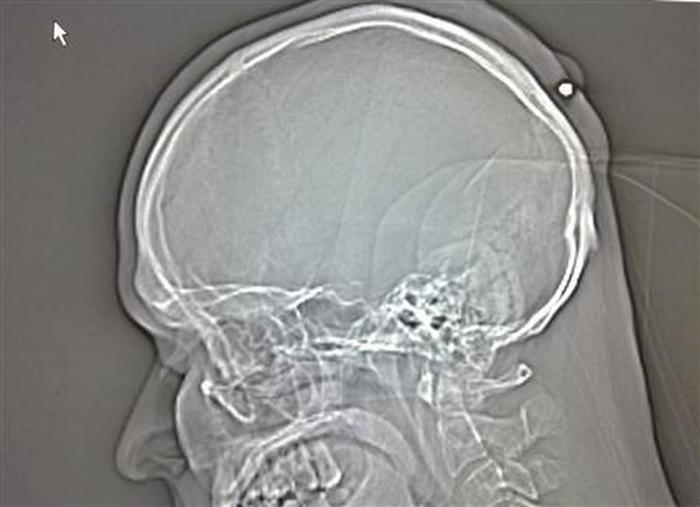

15. Свинцовое похмелье

35-летнему поляку выстрелили в голову, когда тот был пьян, он даже не заметил этого. В итоге пуля была случайно обнаружена пять лет спустя.